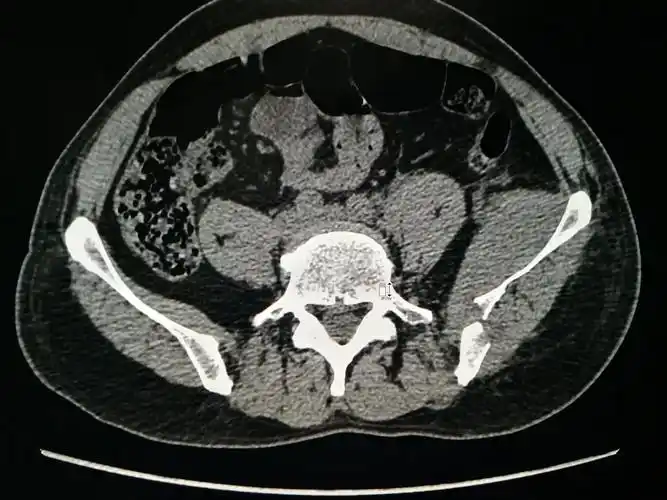

骨盆图片

术前骨盆ct三维重建

患者术前骨盆ct三维重建

ct三维显示:髋臼后壁结构正常

骨盆三维ct重建